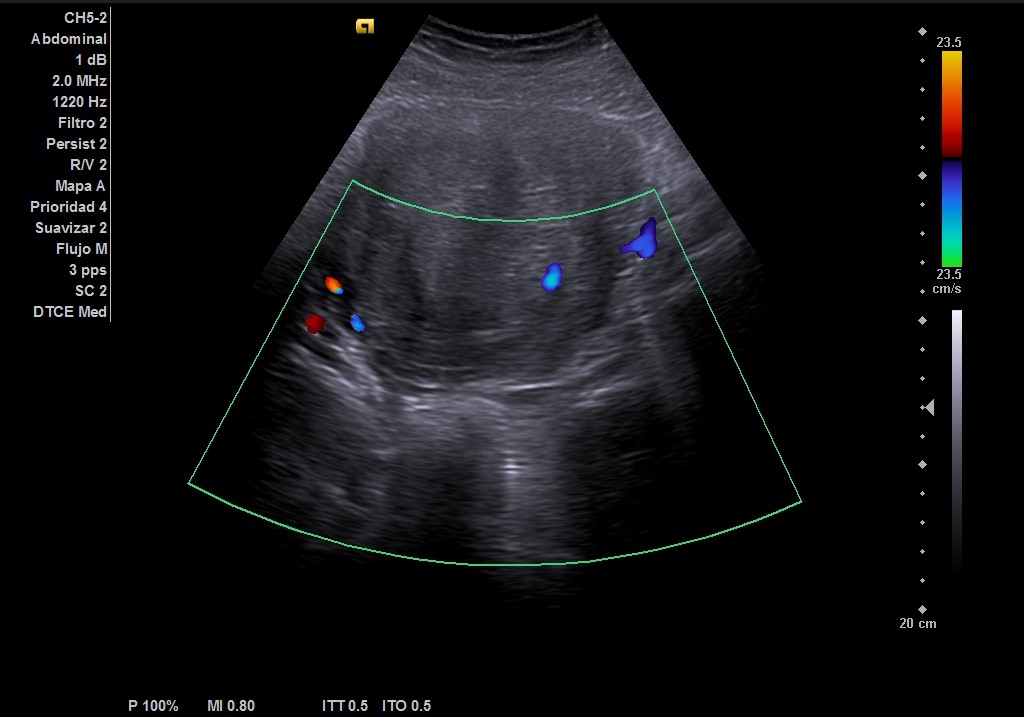

Ecografía abdominal: masa heterogénea de 10 x 10 cm dependiente de útero con vascularización periférica. No se observa la vejiga al estar repleccionada y desplazada por dicha masa. Se vuelve a hacer ecografía con vejiga llena y se observa cómo deforma la pared por efecto masa. Vejiga sin litiasis en su interior, no globo vesical.

Metrorragia secundaria a mioma uterino de gran tamaño.

La paciente es valorada en consulta de patología ginecológica. Le realizan una ecografía abdominal y transvaginal que describe: útero de unos 13 cm de histerectomía. Presenta varios miomas intramurales, destacando uno en cara posterior de 110 x 102 mm que parece contactar con cavidad endometrial sin desplazarla.